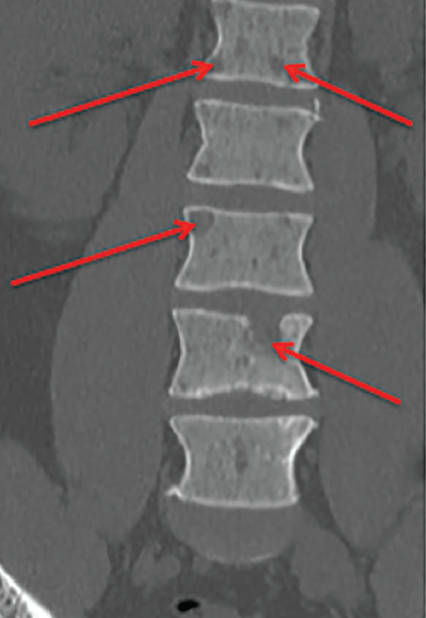

The CT SPINE LUMBAR WO CONTRAST .

- Mild facet arthrosis in the lower lumbar spine.

Facet arthrosis is a degenerative spinal condition like arthritis in which bony enlargements, called osteophytes or bone spurs, grow and enlarge the facet joints.

2. There is a lytic lesion seen in the L1 vertebral body measuring 1.5 cm extending to the inferior endplate and disrupting the cortex.

Also known as bone lesions or osteolytic lesions, lytic lesions are spots of bone damage that result from cancerous plasma cells building up in your bone marrow. Your bones can’t break down and regrow (your doctor may call this remodel) as they should. This makes them thin and creates areas of weaker bones that are vulnerable to fractures.

Lytic bone lesion is a general term used when the bone becomes extremely weak by a disease. Normal bone tissue constantly gets remodeling and repaired from time to time. Lytic lesion of bone is an area where the bone appears to have been eaten away. There are several diseases that can cause destruction of bone area. It can be caused due to malignancy or benign condition.

The three characteristic symptoms of any osteoltyic bone lesions are moderate to severe (mine’s severe) bone pain, pathologic fracture and high level of calcium in blood. It can also increase the risk of spinal cord fractures.

3. Additional lesion is seen at the superior endplate of L2.